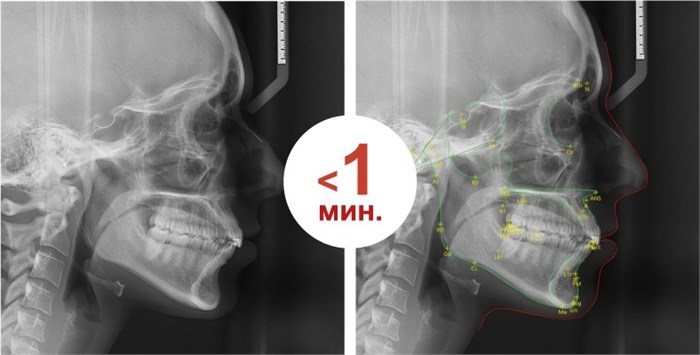

Трассировка вручную занимает более 15 минут, чтобы найти ориентир, разметить контур мягких тканей и выполнить измерения, в то время как EzCeph в EzOrtho завершает этот процесс менее чем за минуту.

Автоматическая трассировка

(EzCeph), решает самую утомительную задачу в процессе диагностики одним нажатием кнопки. Эта функция с помощью искусственного интеллекта находит все ориентиры, необходимые для 15 уникальных методов анализа, предоставляемых в EzOrtho.